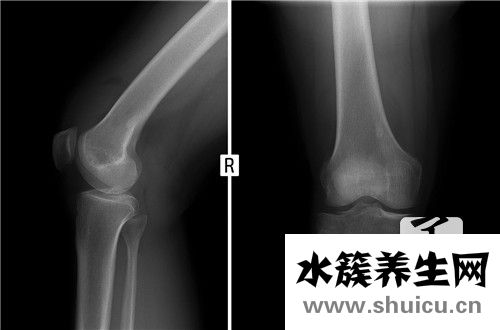

骨刺是骨骼增生的結(jié)果,在X光上面看上去,好像從骨骼周圍長出去一根尖長的東西,因此被稱作「骨刺」。

長出骨刺,意味著骨骼早已進到脆化環(huán)節(jié)。如同設(shè)備用久了,在其中的零件一定會出現(xiàn)損壞,當(dāng)骨骼與骨骼間的軟骨遭受長期性的工作壓力或損害,便會漸漸地喪失延展性、變軟,使左右的骨骼造成損壞,骨骼損壞后,自身會修復(fù),導(dǎo)致優(yōu)質(zhì)蛋白質(zhì)沉定、骨質(zhì)增生。

如果是有肥胖癥問題或者經(jīng)常需要久站的工作中很有可能會給骨節(jié)非常大的壓力,而此壓力會造成 骨節(jié)里的軟骨損壞,使骨節(jié)越來越不穩(wěn)定,骨節(jié)以便提升我們的穩(wěn)定性,會增生骨刺以提升穩(wěn)定性。因此,非常容易增生骨刺的地區(qū)多坐落于負(fù)重的骨節(jié)及其活動力較高的骨骼,如同膝蓋關(guān)節(jié)及其腰椎骨。